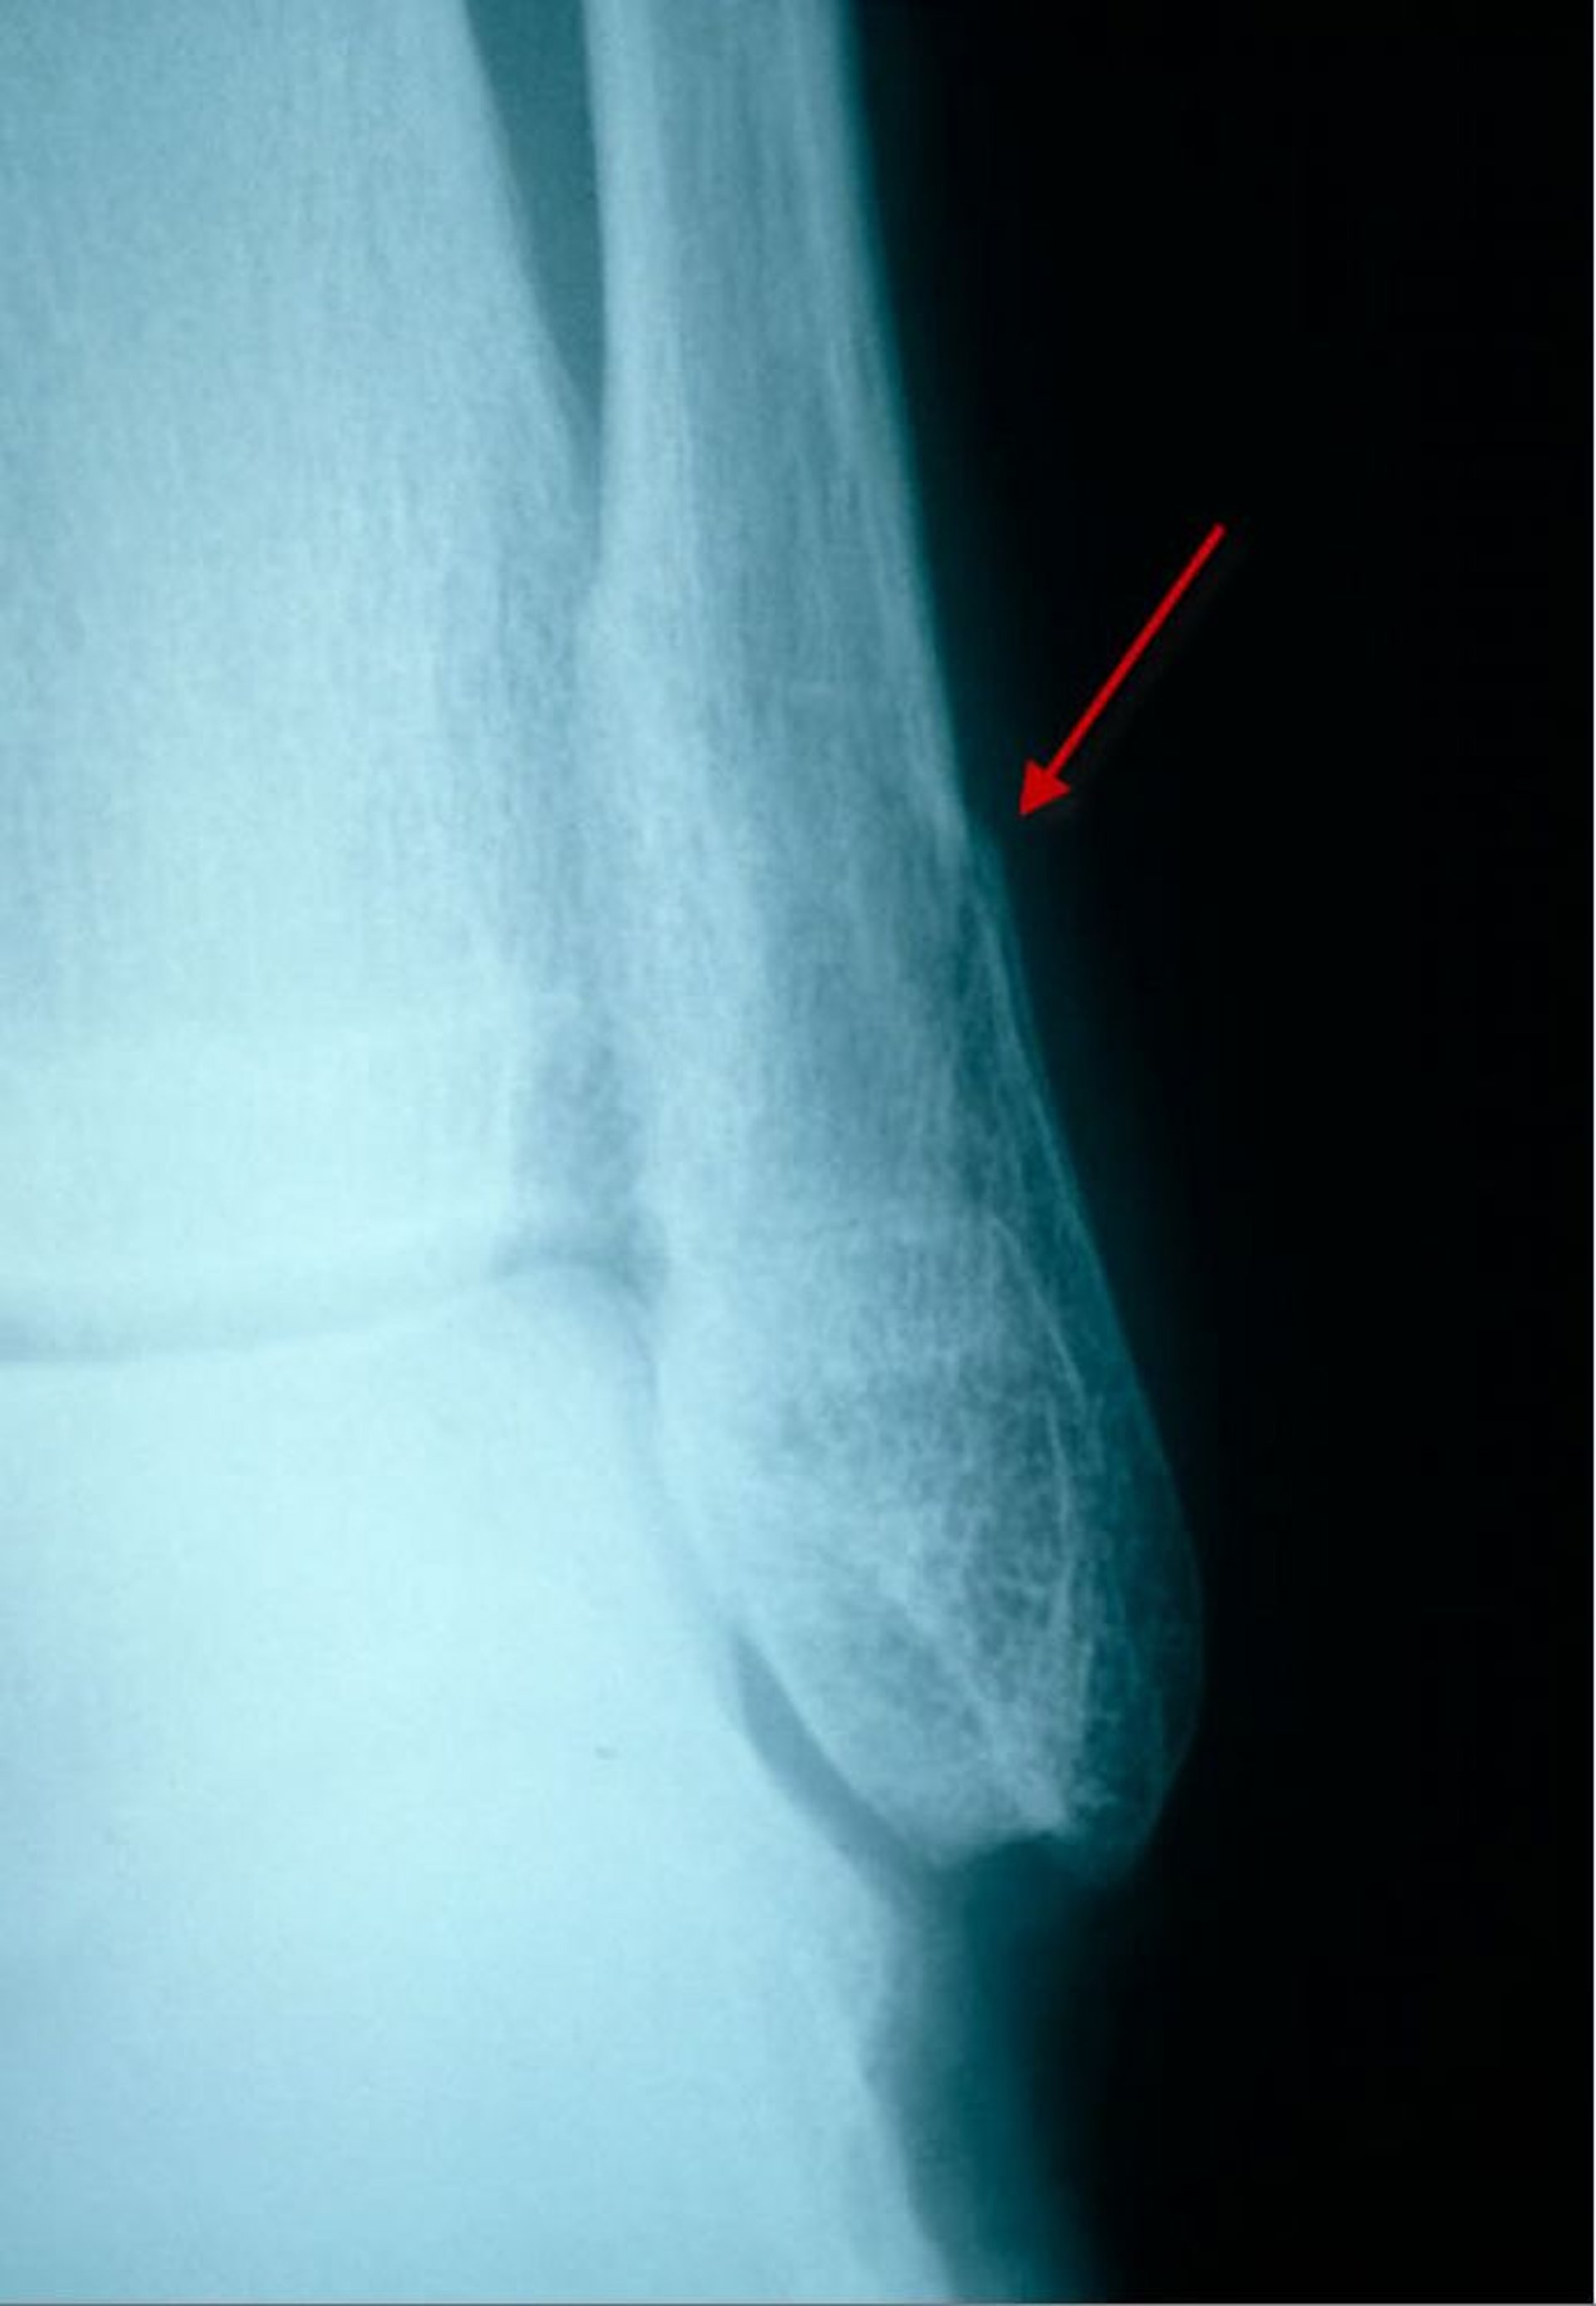

Fractura peroneal distal sutil (vista lateral)

En esta vista lateral, una fractura del peroné distal se visualiza como una pequeña zona radiolúcida y una discontinuidad (salto) de la corteza.